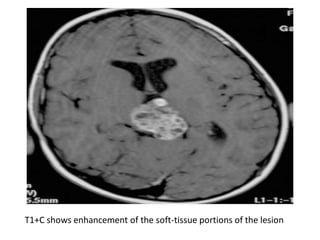

T1+C shows enhancement of the soft-tissue portions of the lesion

T1+C shows enhancementof the soft-tissue portions of the lesion